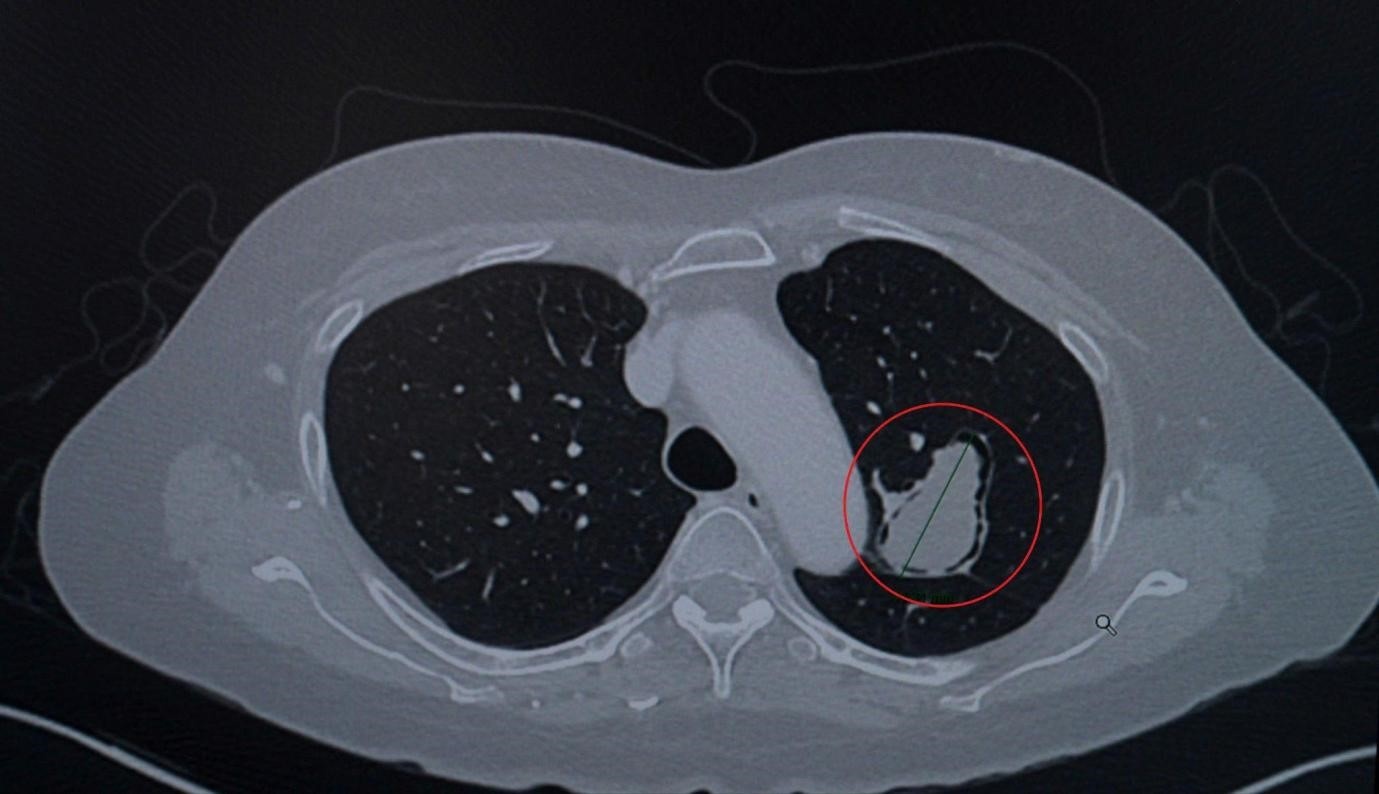

A pulmonary fungal mass (circled in red) located in the upper lobe of the left lung, adjacent to the airway and thoracic aorta, measuring over 4cm in diameter. Photo: FV

The lesion, measuring up to 4.6cm, was situated close to critical structures, posing a risk of vascular invasion or rupture into the airway. This could lead to sudden, life-threatening massive hemoptysis, a complication that may result in rapid death if not promptly managed.